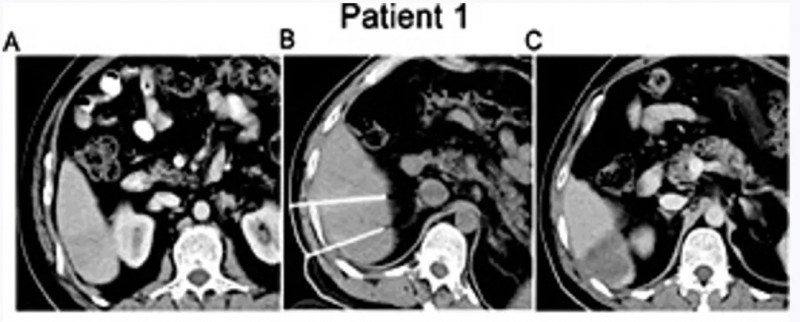

一项发表在《Cellular Physiology and Biochemistry》的研究显示,不可逆电穿孔(IRE)联合同种异体NK细胞治疗IV期肝细胞癌(HCC)具有显著优势。

该研究共纳入40例患者,分为IRE单独治疗组和IRE联合NK细胞组。结果证实,联合治疗组在多个指标上均优于对照组:

- AFP水平显著下降:治疗3个月后,联合组中有11例患者AFP恢复正常;

- 肿瘤体积缩小:联合组肿瘤直径显著小于对照组;

- 疾病控制率(DCR)高达90%,远高于对照组的75%;

- 中位总生存期(OS)延长至10.1个月,相比对照组8.9个月更具优势。

尤其令人振奋的是,有两例患者在联合治疗后达到完全缓解(CR)。一例44岁男性患者,经联合治疗后MRI显示肿瘤无强化,病灶萎缩;另一例52岁女性患者,影像显示肿瘤大面积坏死,疗效持续稳定。

数据来源:Cell Physiol Biochem,医学部汇总

这些结果说明,NK细胞联合局部消融治疗,尤其对于晚期肝癌患者,不仅能有效控制肿瘤进展,还可延长生存期,改善生活质量。